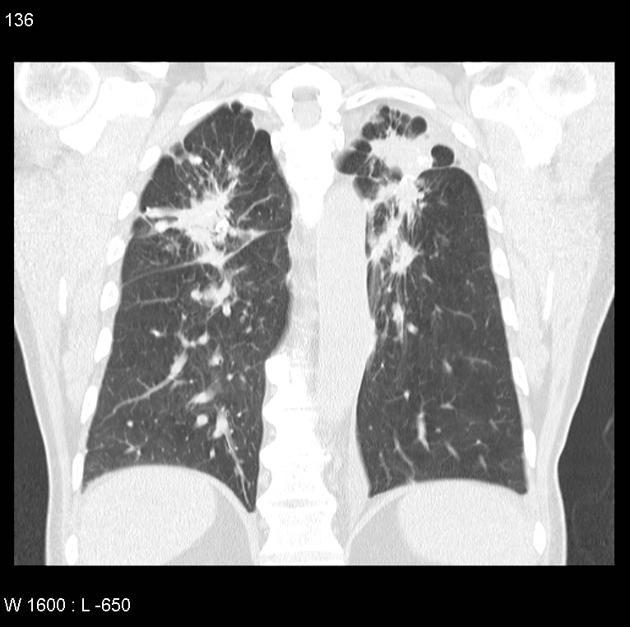

What is this pattern?

What is the etiology?

What disease processes can cause it?

Tree in bud pattern.

Caused by bronchiolar impaction and dilation by pus/mucus/fluid/inflammatory exudate.

Nonspecific- mostly caused by infections/inflammatory conditions. Possibilities include: active TB, MAI, viral pneumonia, fungal pneumonia, obliterative bronchiolitis, cystic fibrosis, immotile cilia syndrome, RA, and neoplastic.